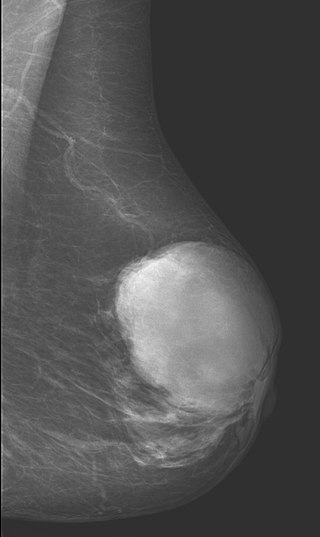

Although ductal carcinoma in situ (DCIS) often shows up as calcification on mammography, it rarely results in a malignancy.

Mammographic calcifications can also be associated with benign disorders such as fat necrosis, sclerosing adenosis, and fibrocystic changes.

Biopsy of calcifications is often necessary to distinguish between benign and malignant conditions.

Invasive ductal carcinoma (IDC) may by detected by physical examination or mammography.

Mammographically identified masses are often 1.0 cm or greater, while masses found by physical exam are typically 2.0 cm or greater.